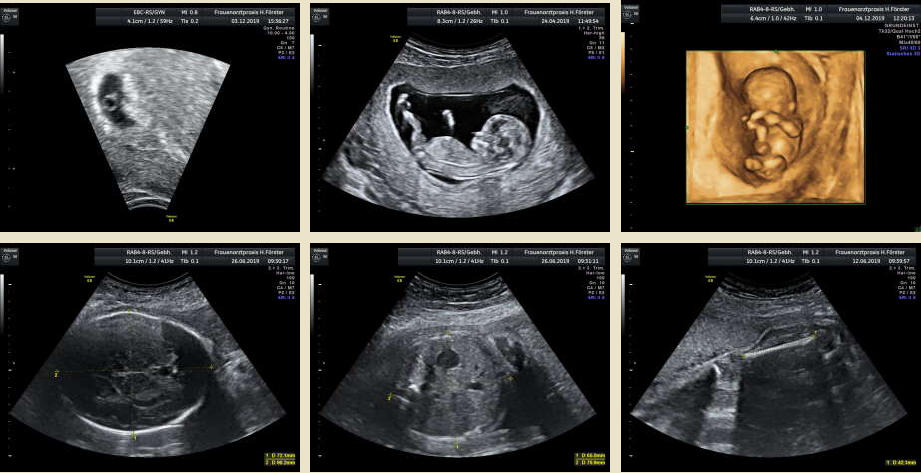

Gynäkologische Grundversorgung Frauenärztliche Krebsfrüherkennungsuntersuchung Nachsorge und supportive Therapie bei bösartigen gynäkologischen Tumoren Impfungen Brustultraschall Ultraschalluntersuchung der weiblichen Genitalorgane Psychosomatische Grundversorgung Chlamydienscreening FOB-Test (früher Hämoccult) Kontrazeption Geburtshilfliche Grundversorgung Geburtshilflicher Basisultraschall Erweiterter Basisultraschall (Organscreening) zw, 18-22.SSW Doppler/Duplexsonografie des fetomaternalen Gefäßsystems Infektionsscreening in der Schwangerschaft CTG (Kardiotokographie) Gynäkologische Grundversorgung Dies umfasst die Abklärung und Behandlung gynäkologischer Erkrankungen. Eine große Rolle dabei spielt das ärztliche Gespräch, ergänzt bei Notwendigkeit durch die gynäkologische Untersuchung oder Untersuchung der weiblichen Brust. In vielen Fällen werden noch Zusatzuntersuchungen durchgeführt (z.B. Ultraschalluntersuchungen, Abstrichentnahmen, Blutentnahmen) oder weiterführende Untersuchungen veranlasst (z.B. Röntgenuntersuchungen). >> zurück << Frauenärztliche Krebsfrüherkennungsuntersuchung Die Krebsfrüherkennungsuntersuchung der Frau ist wahrscheinlich die bekannteste Leistung unseres Fachgebietes. Ab dem Alter von 20Jahren hat jede Frau ein Anrecht auf diese jährliche Untersuchung. Dabei werden der Unterleib der Frau und ab dem Alter von 30Jahren auch die Brüste der Frau systematisch klinisch untersucht. Zusätzlich erfolgte seit vielen Jahren ein Pap-Abstrich vom Gebärmutterhals. So konnten Zellveränderungen meist rechtzeitig erkannt und behandelt werden und es wurde erreicht, daß das früher sehr häufige Zervixkarzinom (Gebärmutterhalskrebs) heute nur noch selten auftritt. Um die Qualität weiter zu verbessern erfolgte 2020 eine Neuordnung des Screenings mit Überarbeitung der Abstrichintervalle und Hinzunahme von HPV-Abstrichen ab 35 als Kassenleistung. >> zurück << Nachsorge und supportive Therapie bei bösartigen gynäkologischen Tumoren Nach Abschluss und oft auch wärend der Primärbehandlung können Probleme auftreten. Es macht also Sinn, sich in regelmäßigen Abständen zu treffen, um das weitere Vorgehen zu planen, eventuell Zusatzuntersuchungen zu veranlassen oder zusätzlich wegen der Beschwerden zu behandeln. Die Nachsorgeuntersuchungen finden anfangs engmaschig statt, später werden die Intervalle länger. >> zurück << Impfungen In Zeiten der Globalisierung, zunehmender Reisefreudigkeit und Zuwanderung werden wir wieder mit Infektionserregern konfrontiert, die wir schon als besiegt geglaubt hatten. Gleichzeitig werden wir immer älter und unser Immunsystem dabei nicht besser. Es reicht nicht, mal eben alle 10Jahre Tetanus zu impfen. Sind Sie geschützt? Wissen Sie was empfohlen ist? Bringen Sie den Impfausweis (auch den alten!!) mit. Wir prüfen Ihren Impfstatus, geben Ihnen Empfehlungen. Die gängigsten Impfstoffe haben wir auch vorrätig und können Sie impfen. >> zurück << Brustultraschall Die Ultraschalluntersuchung der Brust (Mammasonografie) kommt zur Abklärung von krankhaften Veränderungen zur Anwendung oder als Zusatzuntersuchung in der Früherkennung von Brustkrebs bei sehr dichtem Gewebe oder familiärer Vorbelastung. Sie ersetzt nicht das organisierte Mammographiescreening und ist nicht Bestandteil der normalen Krebsfrüherkennung. Es handelt sich um eine schmerzfreie Untersuchung ohne Strahlenbelastung. Die Mammasonografie  ist auch als Wunschleistung (IGeL) möglich. >> zurück << Ultraschalluntersuchung der weiblichen Genitalorgane Die Ultraschalluntersuchung der weiblichen Genitalorgane kommt zur Abklärung von krankhaften Veränderungen des weiblichen Genitales zur Anwendung. Dabei werden mit einer hochfrequenten Vaginalsonde die Organstrukturen im kleinen Becken untersucht. Die Untersuchung ist bei schlanken und sehr jungen Frauen auch vom Bauch aus möglich, die Genauigkeit ist dabei technisch bedingt aber schlechter.  Sie ist nicht Bestandteil der normalen Krebsfrüherkennung. Auch diese Untersuchung ist als Wunschleistung (IGeL) möglich. >> zurück << Psychosomatische Grundversorgung Jede Erkrankung belastet die Seele. Eine seelische Belastung macht den Körper krank. Jeder weiß das. Die Zusammenhänge zwischen dem kranken Körper und der kranken Seele beschreibt die Psychosomatik. Ein "Gordischer Knoten", der nur schwer zu zerschlagen ist, oft ein langer Weg. Ziel ist es, diese Zusammenhänge zu erkennen und den Betroffenen zu helfen ihren Weg zu finden. Oft ist die Zusammenarbeit mit einer Psychologin/ Psychologen nötig. Wichtig ist die Hilfe bei den ersten Schritten. Laufen müssen Sie selbst. >> zurück << Chlamydienscreening Das Bakterium Chlamydia trachomatis kann beim Sex übertragen werden und zu Entzündungen und sogar zur Unfruchtbarkeit führen. Deshalb bezahlen die Krankenkassen bis zum vollendeten 25.Lebensjahr allen sexuell aktiven Frauen einen Suchtest auf Chlamydien. Sie müssen lediglich eine Urinprobe abgeben. Auch in jeder Schwangerschaft wird nach Chlamydien gefahndet. Da Frauen im Normalfall auch im Alter über 25Jahren sexuell aktiv sind und noch schwanger werden wollen bieten wir die Testung auch als Wunschleistung (IGeL) an. Der Test wird dann aus einem Abstrich aus dem Muttermund entnommen, dies kann bei der Krebsfrüherkennung mit gemacht werden. >> zurück << FOB-Test (früher Hämoccult) Im Alter von 50 bis 54Jahren bezahlen die Krankenkassen allen versicherten Frauen einen Stuhltest zur Früherkennung von Darmkrebs oder seiner Vorstufen. Mit 55Jahren können Sie sich entscheiden zwischen zwei Darmspiegelungen im Abstand von 10Jahren oder der Fortführung der Stuhlteste alle 2Jahre. Natürlich kann man Stuhlteste auch zwischen den Darmspiegelungen machen lassen oder auch bei Frauen jünger als 50. Wir bieten dies als Wunschleistung (IGeL) unseren Patienten an. >> zurück << Kontrazeption Ein selbstbestimmtes Leben als Frau ist bei uns in Deutschland eine Selbstverständigkeit. Das war nicht immer so.  Kinder-Küche-Kirche hieß es früher, damals, in der guten alten Zeit. Das ist zum Glück vorbei. Und begonnen hat alles mit der Pille. Frauen konnten endlich über ihren Körper selbst bestimmen, ohne Angst ihre Liebe leben.  Aber die Pille ist nicht alles. Viele Märchen sind im Umlauf, Fehlinformation. Aber auch fehlendes Wissen zu Risiken.  Wir beraten Sie gern. >> zurück << Geburtshilfliche Grundversorgung In der Schwangerenberatung werden die werdenden Muttis gemäß den geltenden Mutterschaftsrichtlinien vom Anfang der Schwangerschaft bis zur Abschlussuntersuchung (6-8 Wochen nach der Geburt) betreut. >> zurück << Geburtshilflicher Basisultraschall Nach Vorgabe der Mutterschaftsrichtlinie sind sind in der Schwangerschaft 3 Ultraschalluntersuchungen vorgesehen. Diese finden in der 8.-12. SWW, in der 18,- 22. SSW und in der 28.-32.SSW statt. Dabei werden der Zustand des Embryos/ Feten, des Fruchtwassers und der Plazenta beurteilt. >> zurück << Erweiterter Basisultraschall (Organscreening) zw. 18-22.SSW Bei der zweiten Ultraschalluntersuchung (zw.18.-22. SSW) erfolgt ein erweitertes Screening mit Beurteilung der Organstrukturen des Kindes. Diese Untersuchung ist Kassenleistung, kann aber bei Wunsch auch Abgewählt werden, dann wird nur der Basisultraschall durchgeführt. >> zurück << Doppler/Duplexsonografie des fetomaternalen Gefäßsystems Bei Aüffälligkeiten im Schwangerschaftsverlauf oder auch bei bestimmten Vorerkrankungen oder Erkrankungen in einer früheren Schwangerschaft kann es notwendig sein die Durchblutung des Mutterkuchens und der Gefäße des Kindes zu Untersuchen. Hier kommt das Dopplerverfahren als Erweiterung des normalen geburtshilflichen Ultraschalls zum Einsatz. Dies erlaubt eine schnelle Zustandsbeurteilung des Kindes pepaart mit einer zeitlich begrenzten Vorhersage über die weitere wahrscheinliche Entwicklung. Bei entsprechender Indikation ist diese Untersuchung als Kassenleistung abrechenbar. >> zurück << Infektionsscreening in der Schwangerschaft Die Suche nach Krankheitserregern im Krankheitsfall ist Kassenleistung. Routinemäßig prüfen wir Ihren Schutz vor Röteln und Windpocken , in jeder Schwangerschaft erfolgt ein Test auf Chlamydien. Zusätzlich empfehlen wir jeder Schwangeren einen Test auf eine Besiedelung mit Gruppe-B-Streptokokken vor der Geburt. Diese Streptokokken können zu schweren Atemwegsinfektionen des Neugeborenen führen. Eine vorbeugende Behandlung bei positivem Test kann dann unter der Geburt erfolgen. Bei Wunsch kann auch ein erweitertes Erregerscreening über unser Labor erfolgen (Wunschleistung). Eine wichtige Rolle spielt auch die Kontrolle auf einen Schutz gegen eine Toxoplasmoseinfektion. Bei fehlendem Schutz empfielt sich die regelmäßige Testung aus dem Blut auf eine frische Infektion. Auch dies ist eine Privatleistung, wird aber von den meisten Kassen erstattet. Eine nicht erkannte und somit nicht behandelte Erstinfektion in der Schwangerschaft kann zu schweren Schäden beim Kind führen. >> zurück << CTG Ab etwa der 30.Schwangerschaftswoche können wir bei Notwendigkeit im Ramen der Schwangerschaftsvorsorge die kindlichen Herztöne (Kardiographie) und simultan dazu die die Spannung der mütterlichen Bauchdecke (Wehenschreiber, Tokographie) graphisch darstellen. Das nennt man zusammen Kardiotokographie oder kurz einfach CTG. Die Auswertung des CTG‘s erfolgt nach dem Fisher-Score (Punkte-System) sowie nach qualitativen Kriterien und erlaubt uns eine gute Zustandsbeurteilung des Kindes in den späteren Schwangerschaftswochen. >> zurück <<